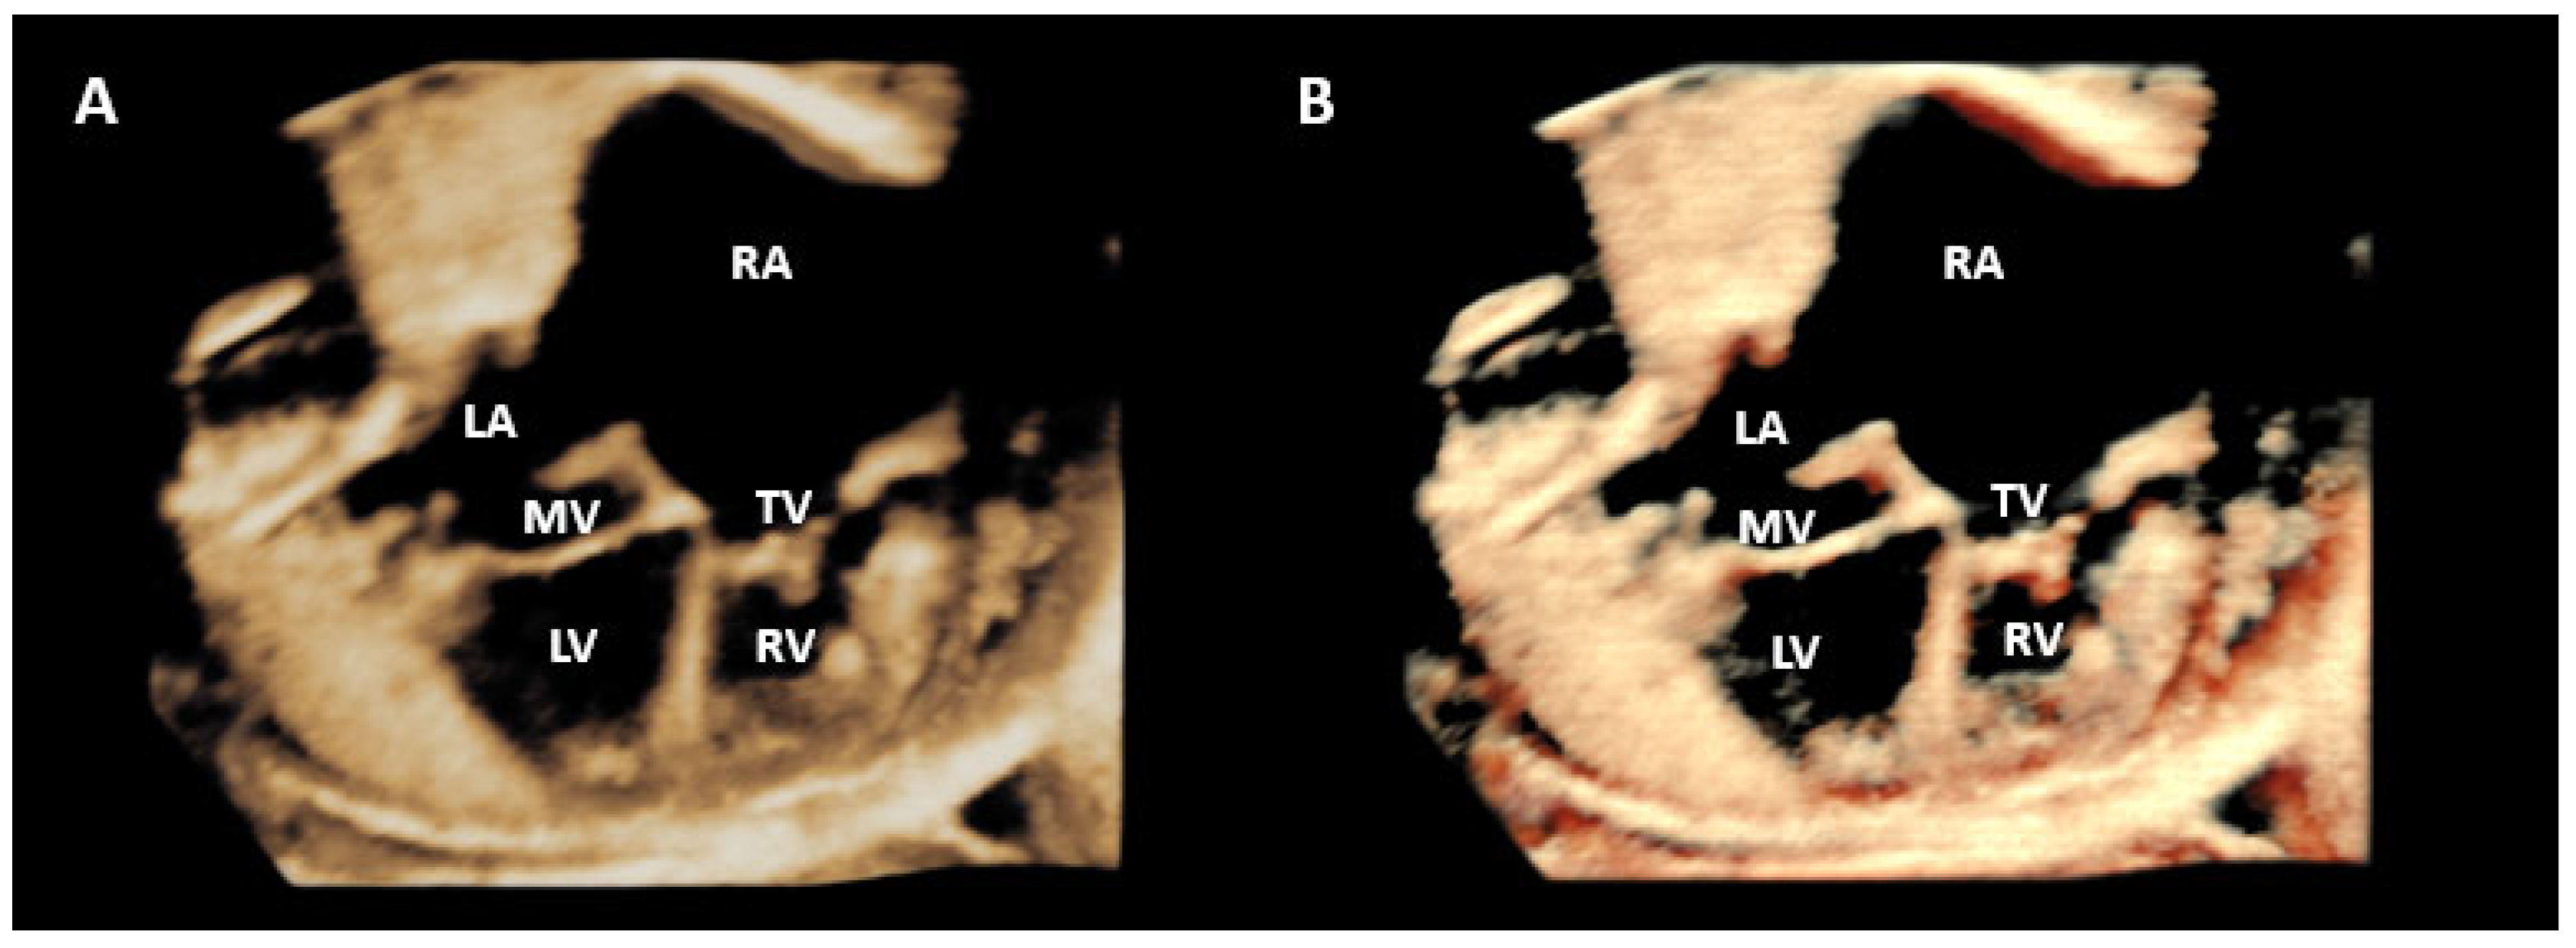

- Yagel S, Benachi A, Bonnet D, Dumez Y, Hochner-Celnikier D, Cohen SM; et al. Rendering in fetal cardiac scanning: The intracardiac septa and the coronal atrioventricular valve planes. Ultrasound Obstet Gynecol. 2006, 28, 266–274.

- Araujo Júnior E, Tonni G, Bravo-Valenzuela NJ, Da Silva Costa F, Meagher S. Assessment of Fetal Congenital Heart Diseases by 4-Dimensional Ultrasound Using Spatiotemporal Image Correlation: Pictorial Review. Ultrasound Q. 2018, 34, 11–17.

- Malho A, Ximenes RS, Bravo-Valenzuela NJ, Araujo Júnior E. Spatio-Temporal Image Correlation: Three-Dimensional Imaging for Fetal Cardiac Screening and Congenital Heart Disease Assessment. Arq Bras Cardiol. 2024;121(4):e20230580.

- Magioli Bravo-Valenzuela NJ, Malho AS, Nieblas CO, Castro PT, Werner H, Araujo Júnior E. Evolution of Fetal Cardiac Imaging over the Last 20 Years. Diagnostics (Basel). 2023, 13, 3509.